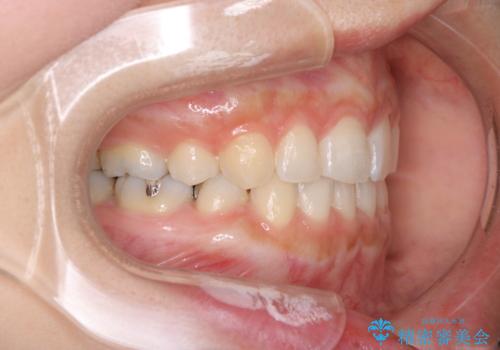

- 口元が出てるのが気になるとのことで来院されました。

上下左右前から4番目の歯を抜歯して前歯を後方に下げて、口元を下げる計画としました。